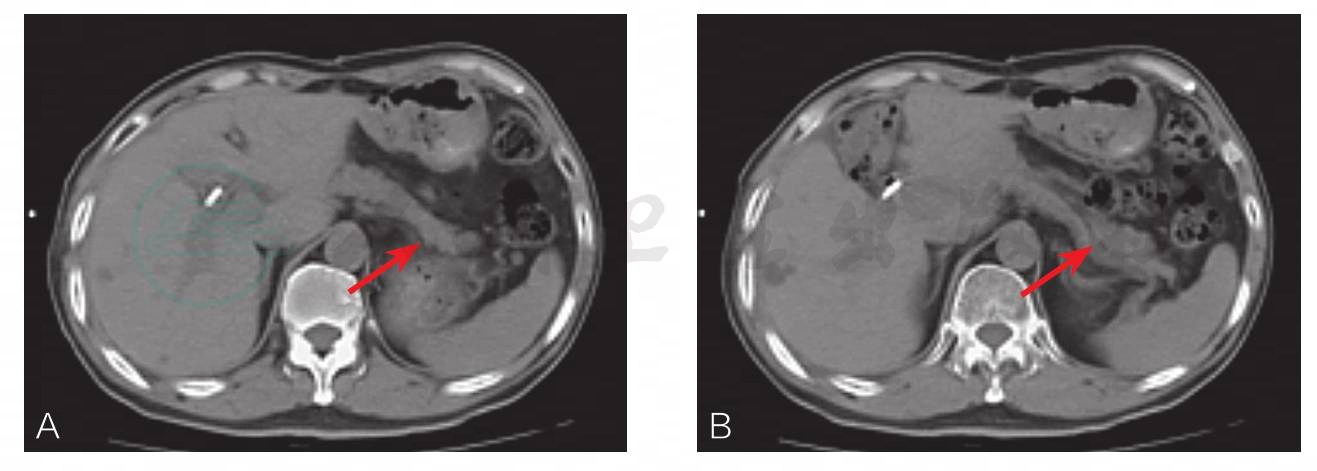

增强CT提示:胰头部肿大,强化明显,与肠系膜上静脉关系紧密;胆管系统扩张,胰管部分轻度扩张(图1)。

图1 患者术前增强CT影像

胰头部肿大(圆圈所指),强化明显,与肠系膜上静脉关系紧密;胆管系统扩张,胰管部分轻度扩张